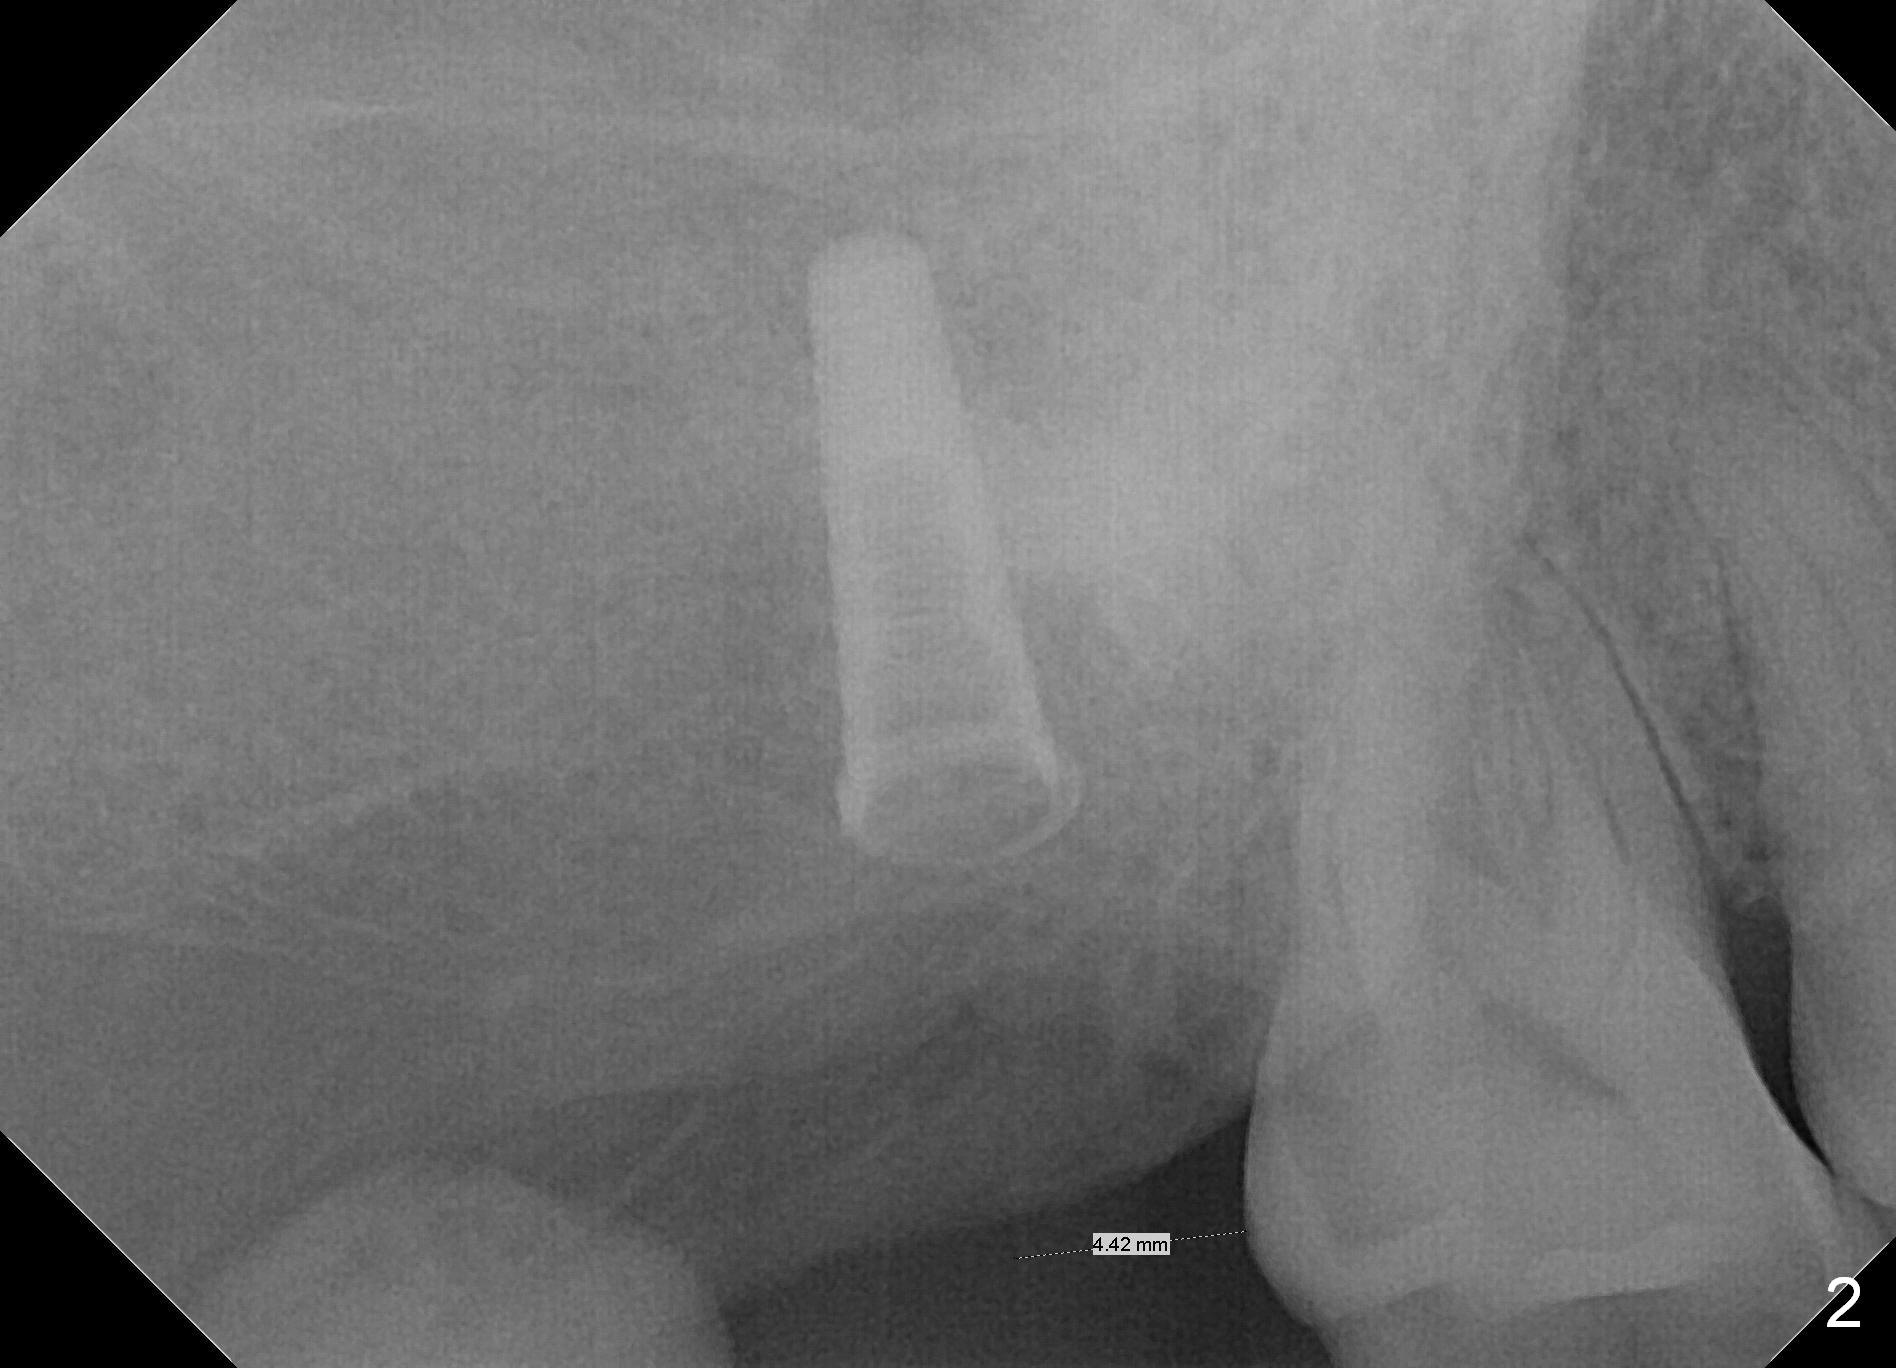

The edentulous ridge at the site of #2 is wide. Magic split is used to gain access, test bone density and start osteotomy for 9 mm (gingival level). A 1.6 mm drill is used to extend the osteotomy for depth of 13 mm. The osteotomy position and trajectory is confirmed with a parallel pin (Fig.1), which is ideal. The remaining osteotomy is finished with Magic Expanders from 3 to 4.3 mm for 15 mm. The trajectory is confirmed again with insertion of a 4.5x11 mm dummy implant at the depth of 15 mm (Fig.2). When a definitive IBS implant (5x13 mm) is placed with insertion torque >45 Ncm, the distal coronal end is not subcrestal (Fig.3-5). As the implant is placed deeper, it started to lose primary stability. When a pair abutment is placed, it keeps turning. Finally a healing abutment (6x3 mm) is placed unstable. In brief, taking several X-ray films help control osteotomy and implant position and trajectory. The implant is unstable 7 months postop (Fig.6). With local anesthesia, the implant is placed deeper by 1 mm with apparent increase in torque and a 6x4 healing abutment placed. The implant is stable 11 months postop. With 5.5x4(4) mm abutment placed, impression is taken. PA and BW will be taken after cementation of the crown. There is no bone loss 9 months post cementation (Fig.7). Return to Upper Molar Immediate Implant, 18-20, 29,30 Xin Wei, DDS, PhD, MS 1st edition 01/09/2017, last revision 08/15/2021